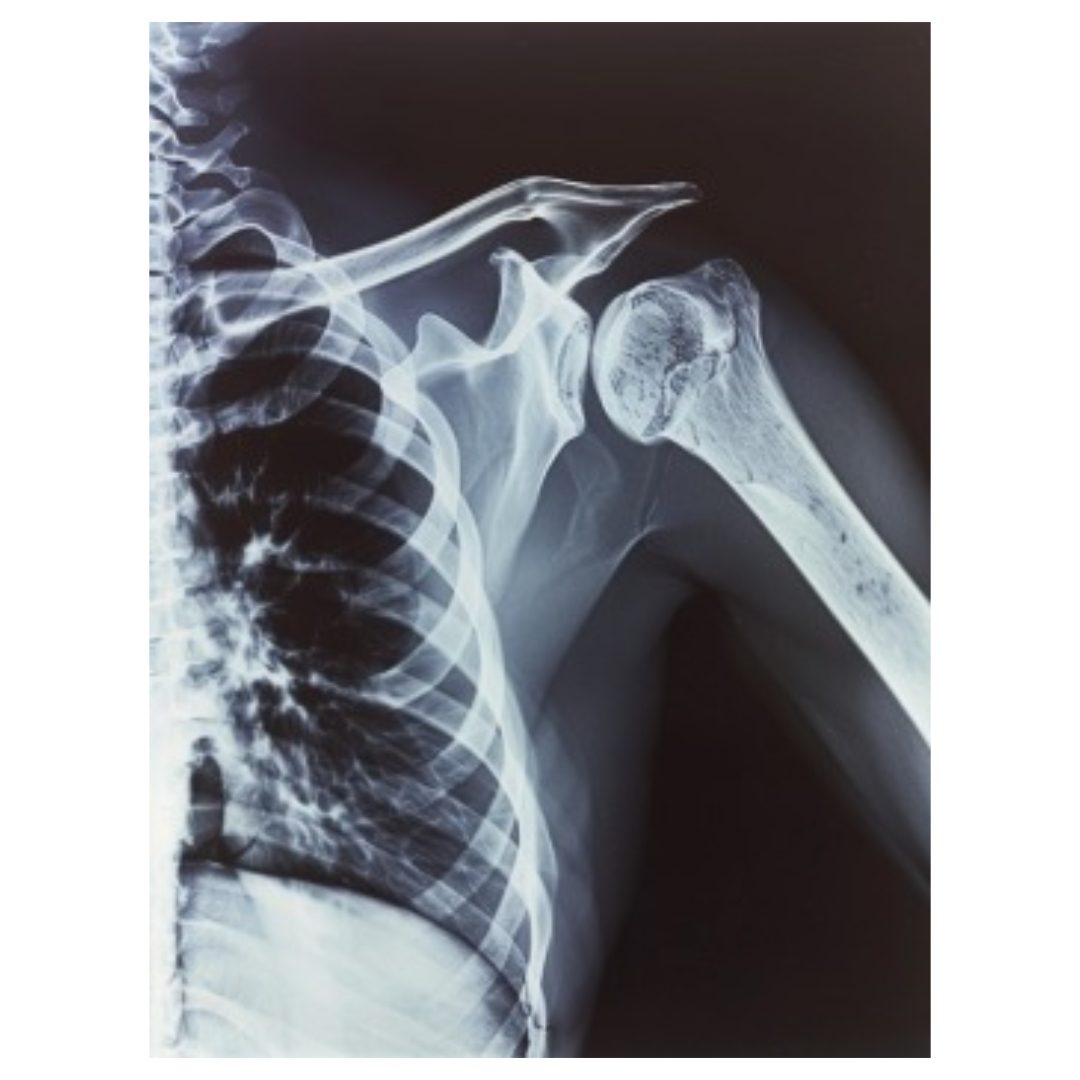

9. 어깨통증 치료법 - 수술

통증이 너무 심하거나, 회복이 어려운 상태일 경우에는 수술이 필요할 수 있습니다. 회전근개 파열, 관절낭염, 또는 어깨 탈구와 같은 문제는 수술적인 치료가 필요한 경우가 많습니다.

수술은 마지막 수단으로 생각하셔야 하며, 모든 비수술적 치료가 실패했을 때 선택하는 방법입니다. 하지만 회복이 빠르고, 장기적인 결과가 좋은 경우도 많으니 의료진과 상의하여 결정하시면 됩니다.